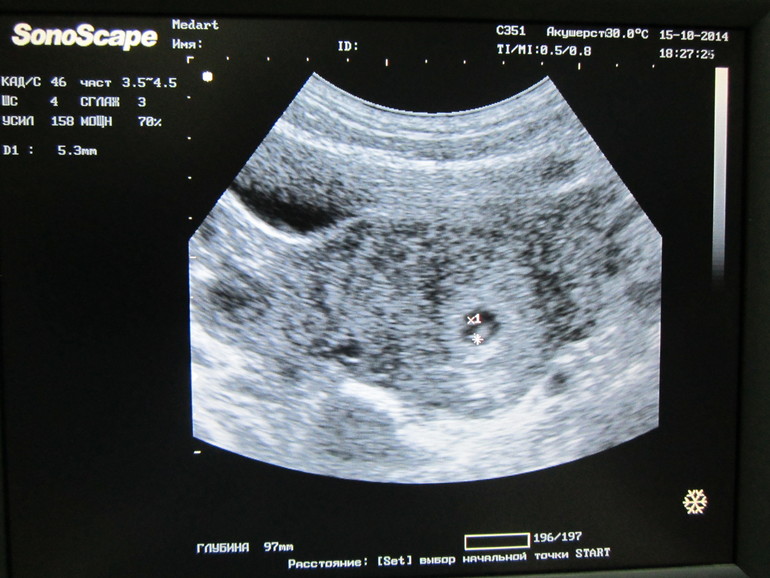

Вчера на УЗИ были

боялось страшно! Постоянно себя накручивала, что всё плохо, что беременность внематочная, что малыша нет или сердце не бьётся...

Ходила на УЗИ к своему врачу, который вёл прошлую беременность. Очень рад за нас. Посмотрел всё хорошо у нас.

Плод 5,3 мм. Сердце уже бьётся. Врач почему-то говорит - "рано!", говорит, плод маленький по размерам, ели тянет на 4 недели, а сердце уже чётко бьётся, несколько раз проверял, говорит "думал, показалось". А я счастлива, так боялась, что сердце ещё биться не будет, и снова вся на нервах)) сказал, прийти на контроль в 8 недель. И на учёт могу вставать с 7 нед., сказала, что раньше 10 точно не приду)) если б не скрининг, ещё позже б пришла)

Ну, а это первое фото нашей масявки, сыном у меня фото нет, в этот раз всех достану, требовать буду!)) Рассказала о болях, сказал, что может быть угроза, и что он не советует на таком сроке сохранять. Но на УЗИ нет угрозы, говорю, может из-за того, что малого поднимаю, он у нас 16 кг. за, что он меня отругал, сказал, что так могу беременность сорвать( надо что-то теперь думать, так чтоб малый сам в ванную залез и в кроватку...

Когда УЗИ рассматривали, говорю а с Кириллом было другой формы яйцо, было вытянутое, плоское, он говорит "угроза была", а я в шоке! почему мне тогда никто этого не говорил, я думала это норма, вся беременность оно таким было! обсудили прошлые роды, тоже много для себя узнала, оказалось у меня было малоплодие и походу инфицирование, но чего все тогда молчали и говорили, всё хорошо... Я видела, что вод очень мало было, очень! и зелёные были, грязные, тогда мне сказали, что всё хорошо(( ну да ладно, ведь всё хорошо сейчас)